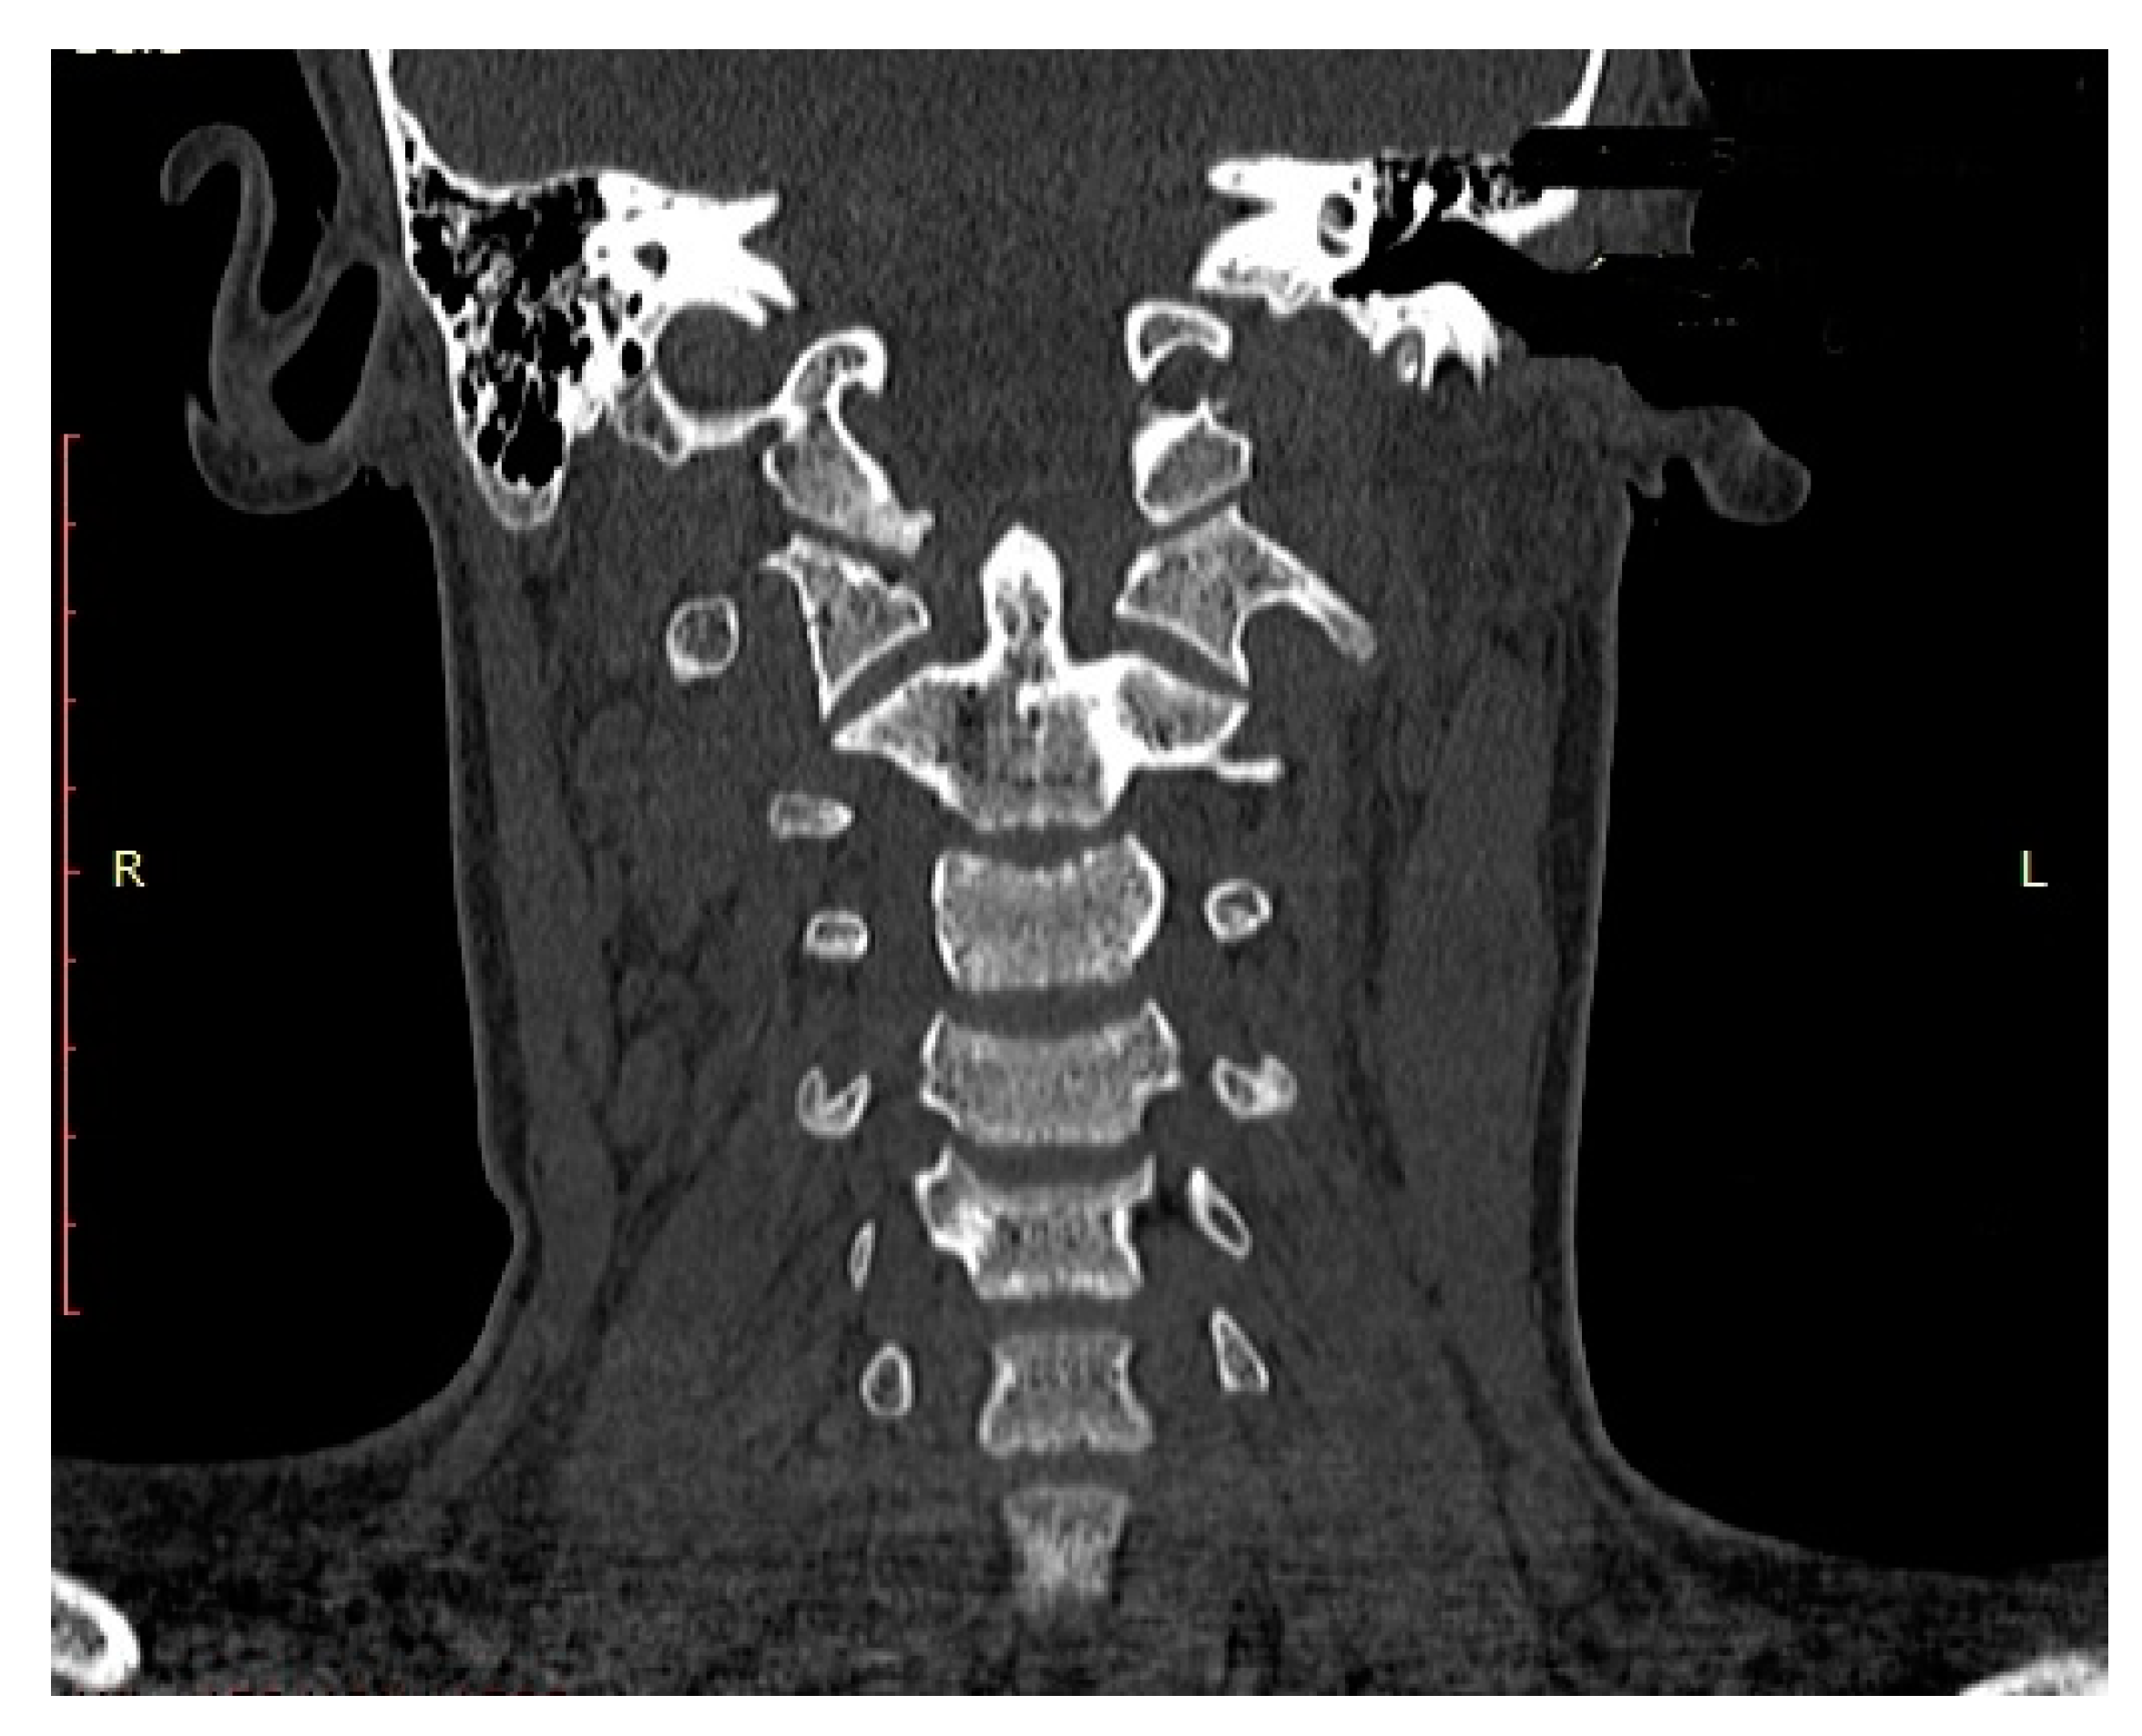

| P.P. | M | 15.2 | III (unstable) | IIB | Road traffic accident (car passenger) | Fracture frontal bone, fracture frontal sinus, contusion of frontal lobe | Halo-vest immobilization: 12.5 weeks |

| K.D. | F | 15 | III (unstable) | IIB | Pedestrian hit by car | Lung contusion, brain concussion, multiple abrasions | Halo-vest immobilization: 13 weeks |

| R.M. | F | 18 | I (unstable) | IIB | Road traffic accident (car passenger) | Pneumothorax, neurogenic vocal cord injury, post-traumatic aphasia | Halo-vest immobilization: 14 weeks |

| S.D. | M | 14.7 | III (stable) | IIA | Road traffic accident (car passenger) | Fracture of frontal bone, fracture of nasal bone, subdural hematoma | Minerva-brace immobilization |

| B.W. | F | 16 | I (stable) | IIA | Fall from a height | Fracture of frontal bone, fracture of nasal bone, subarachnoid hemorrhage, fracture of transverse process Th3-5, fracture of radius | Minerva-brace immobilization |

| M.O. | M | 16.1 | I (stable) | IIA | Bicycle incident | Fracture frontal bone, fracture maxillary sinus, fracture orbit, metacarpal fracture | Minerva-brace immobilization |